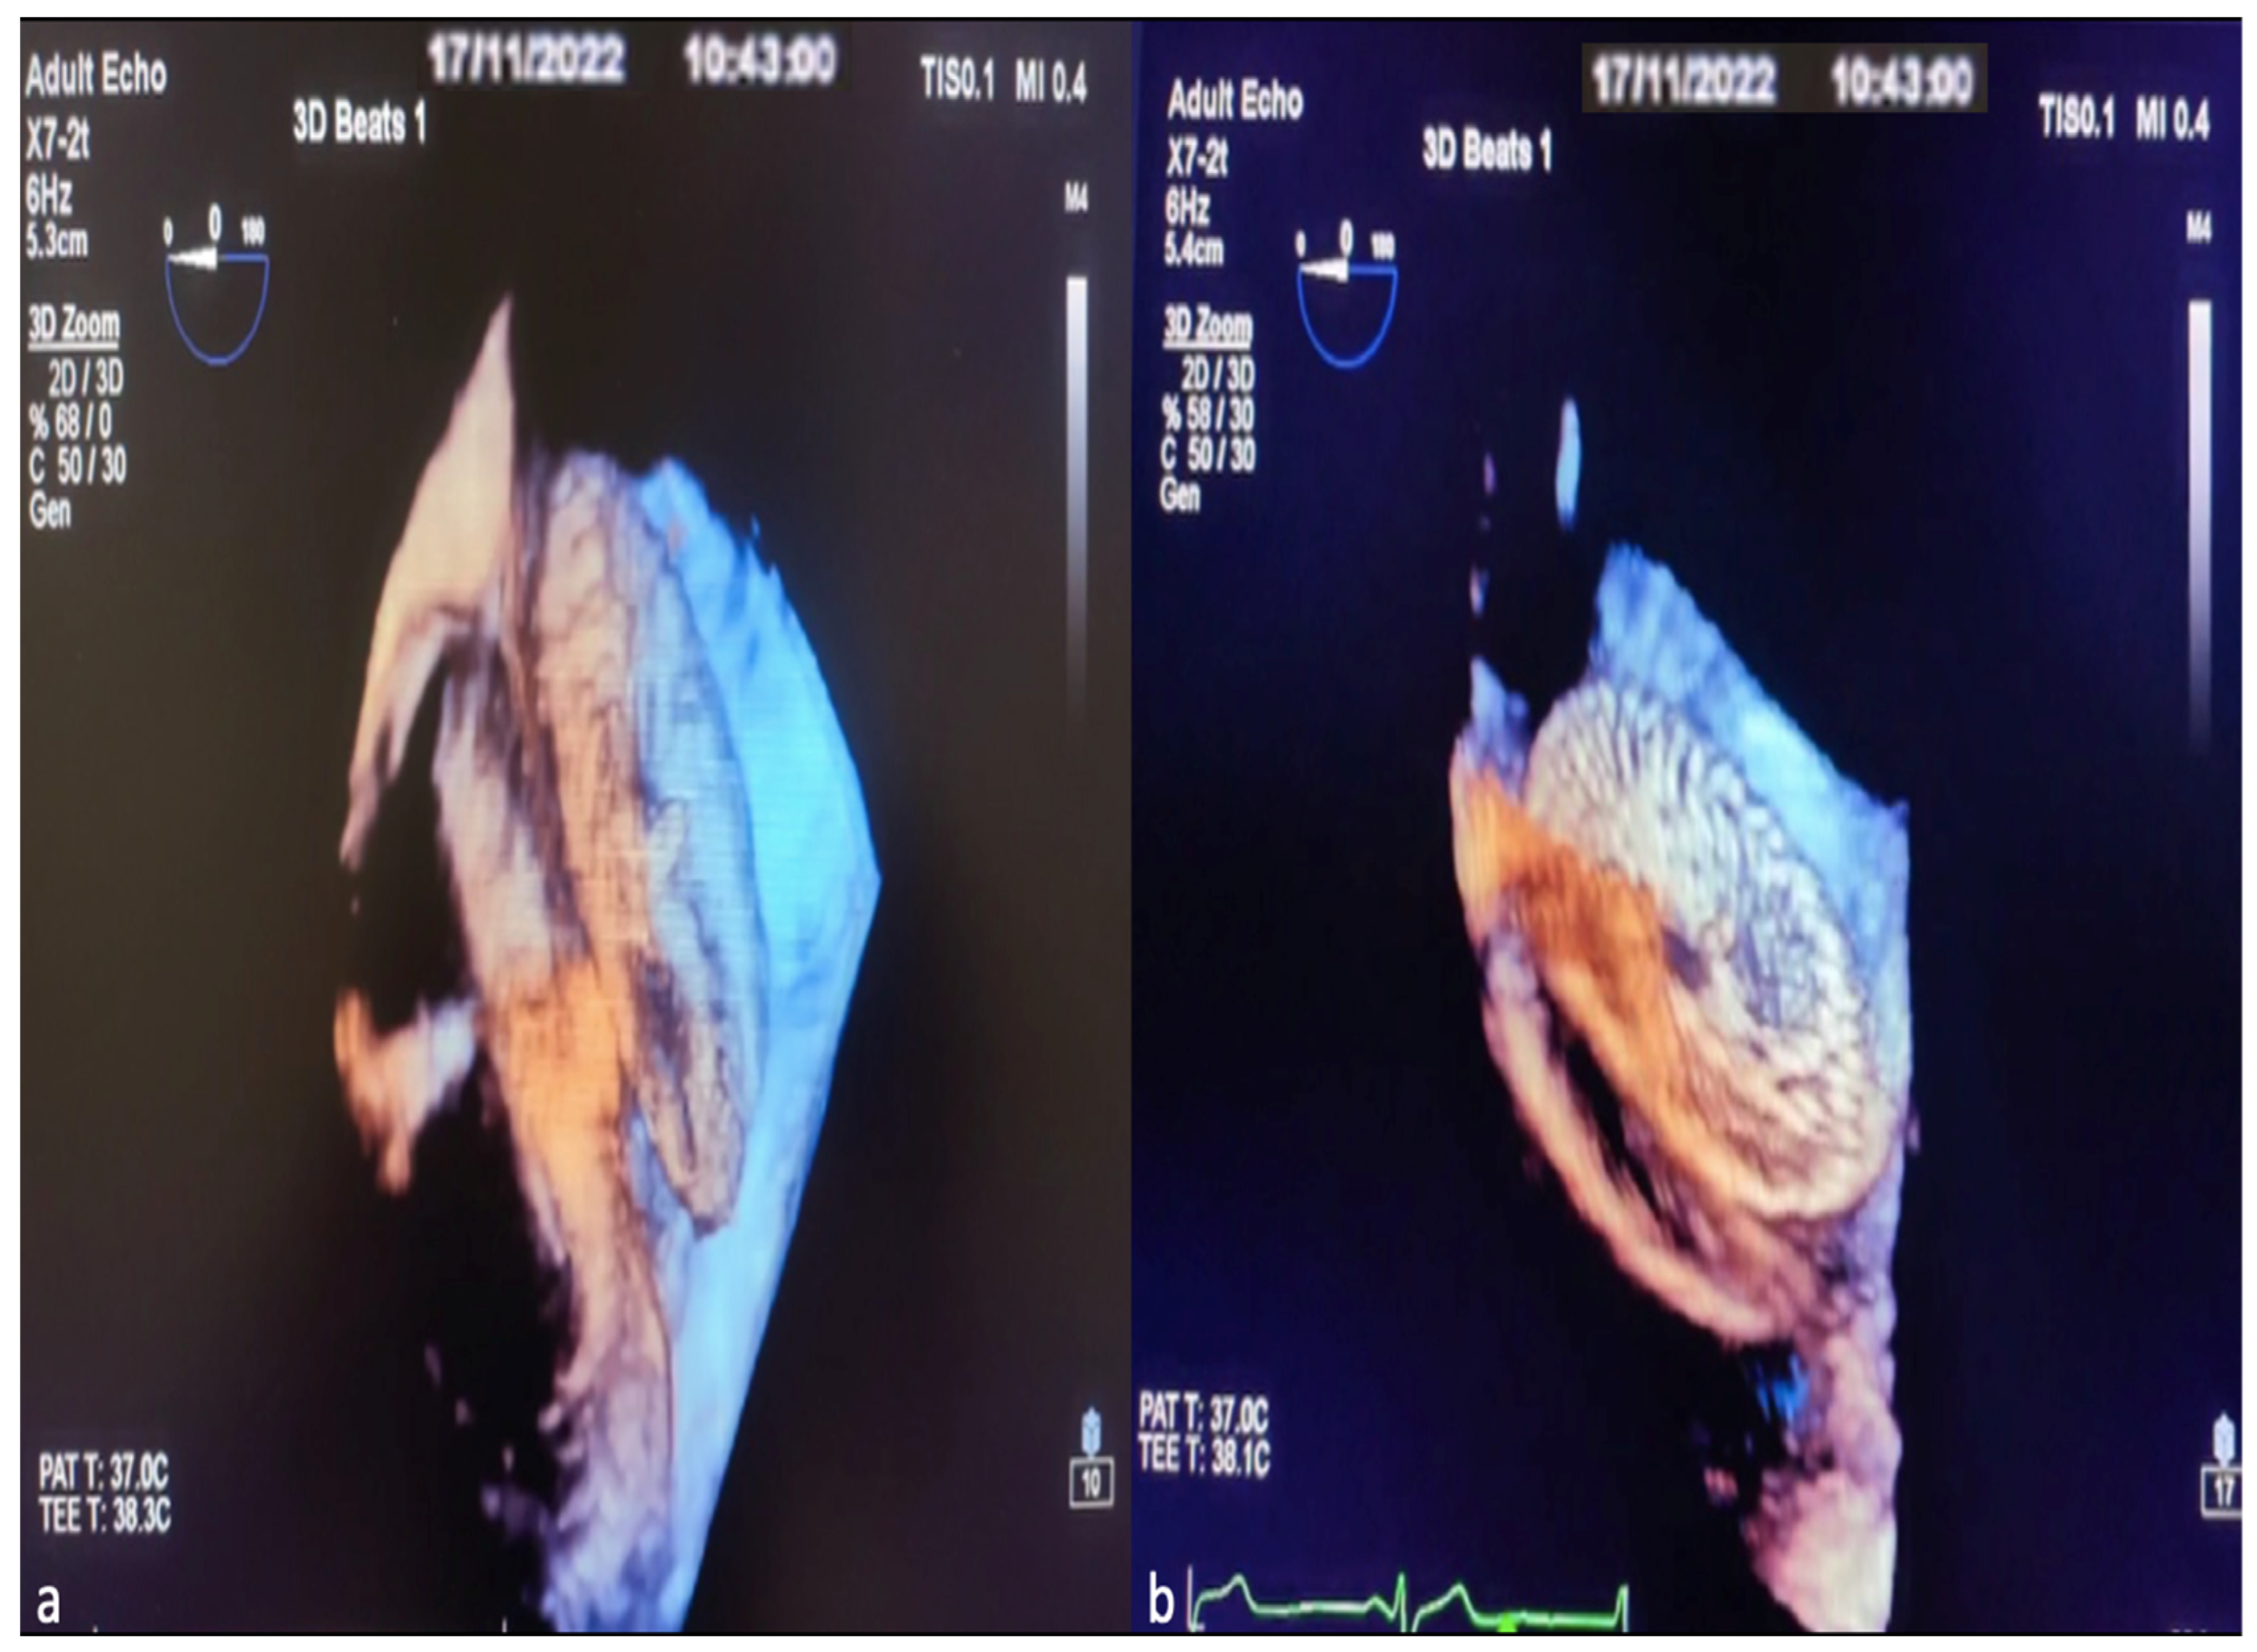

Finally, after observing that the device was in the appropriate position and place, the stability of the device and the rims were checked with the Minnesota maneuver (the device is moved back and forth with the help of the catheter). Once the optimal implantation was determined, the device was released, and the procedure was completed. The 3D TEE image of the ASD occlusion device before release and after release is shown in Figure 5a,b.

Figure 5.

Images of ASD occlusion device closure with intraoperative 3D TEE procedure. View the implanted device from the lateral interatrial septum before it is separated from the delivery system (a). Image of the ASD occlusion device after leaving the delivery system (b).